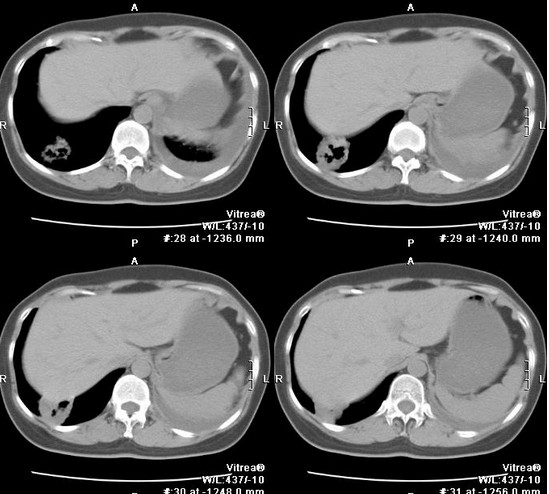

胸部CT扫描多呈类圆形的厚壁脓腔,脓腔内可有液平面出现,脓腔内壁常表现为不规则状,周围有模糊炎性影。